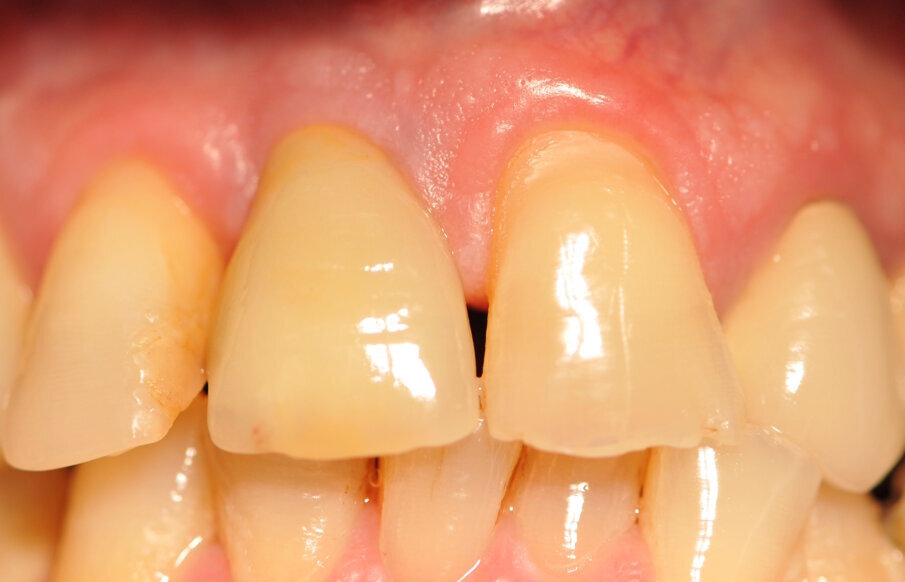

Fig. 9_Situazione clinica prima della cementazione della corona definitiva.

Paziente di sesso maschile di 60 anni di età giunto alla nostra osservazione per una edentulia parziale dovuta all’assenza dell’elemento 1,1. La situazione clinica è resa esteticamente e funzionalmente complicata dalla assenza dell’elemento 2,2 che considerato lo spostamento dei denti contigui comporta un aumentato spazio per la sostituzione protesica dell’elemento 1.1. Si effettua dopo rx di controllo il posizionamento di un impianto osteintegrato GTB diametro 3,6 x 9 mm ,con posizionamento, come da protocollo, 1,5 mm sottocrestale ed inserzione immediata di moncone easy abutment slim 3,4 x 7 mm altezza gengivale 3,5 mm. angolato a 10 gradi (Easy Abutment Slim – GTB Plan1Health Amaro, UD, Italy). Con l’ausilio di una cappetta easy si costruisce e si cementa, con tecnica extraorale, una corona provvisoria in resina acrilica con forma a pontic su elemento 1.1 in modo da eseguire un carico immediato e fornire al paziente una estetica immediata (Figg. 1-3). Dopo 12 settimane ad avvenuta osteointegrazione si provvede all’impronta definitiva eseguita a livello abutment con elastomero di precisione Aquasyl Monophase (Dentsply) e con idonea cappetta easy (GTB Plan1Health Amaro, UD, Italy). La stessa cappetta easy viene utilizzata dal laboratorio odontotecnico come cappetta da sovrafusione garantendo standard di precisione stabiliti industrialmente (Figg. 4-8). La corona costruita in lega preziosa e porcellana viene cementata dopo una settimana, fatte le prove estetiche e occlusali necessarie sul paziente. I controlli a distanza di 4 anni, sia radiografici che clinici, confermano la stabilità dell’osso intorno all’impianto e la mancanza di perdita di tessuto gengivale attorno allo stesso (Figg. 9-11).